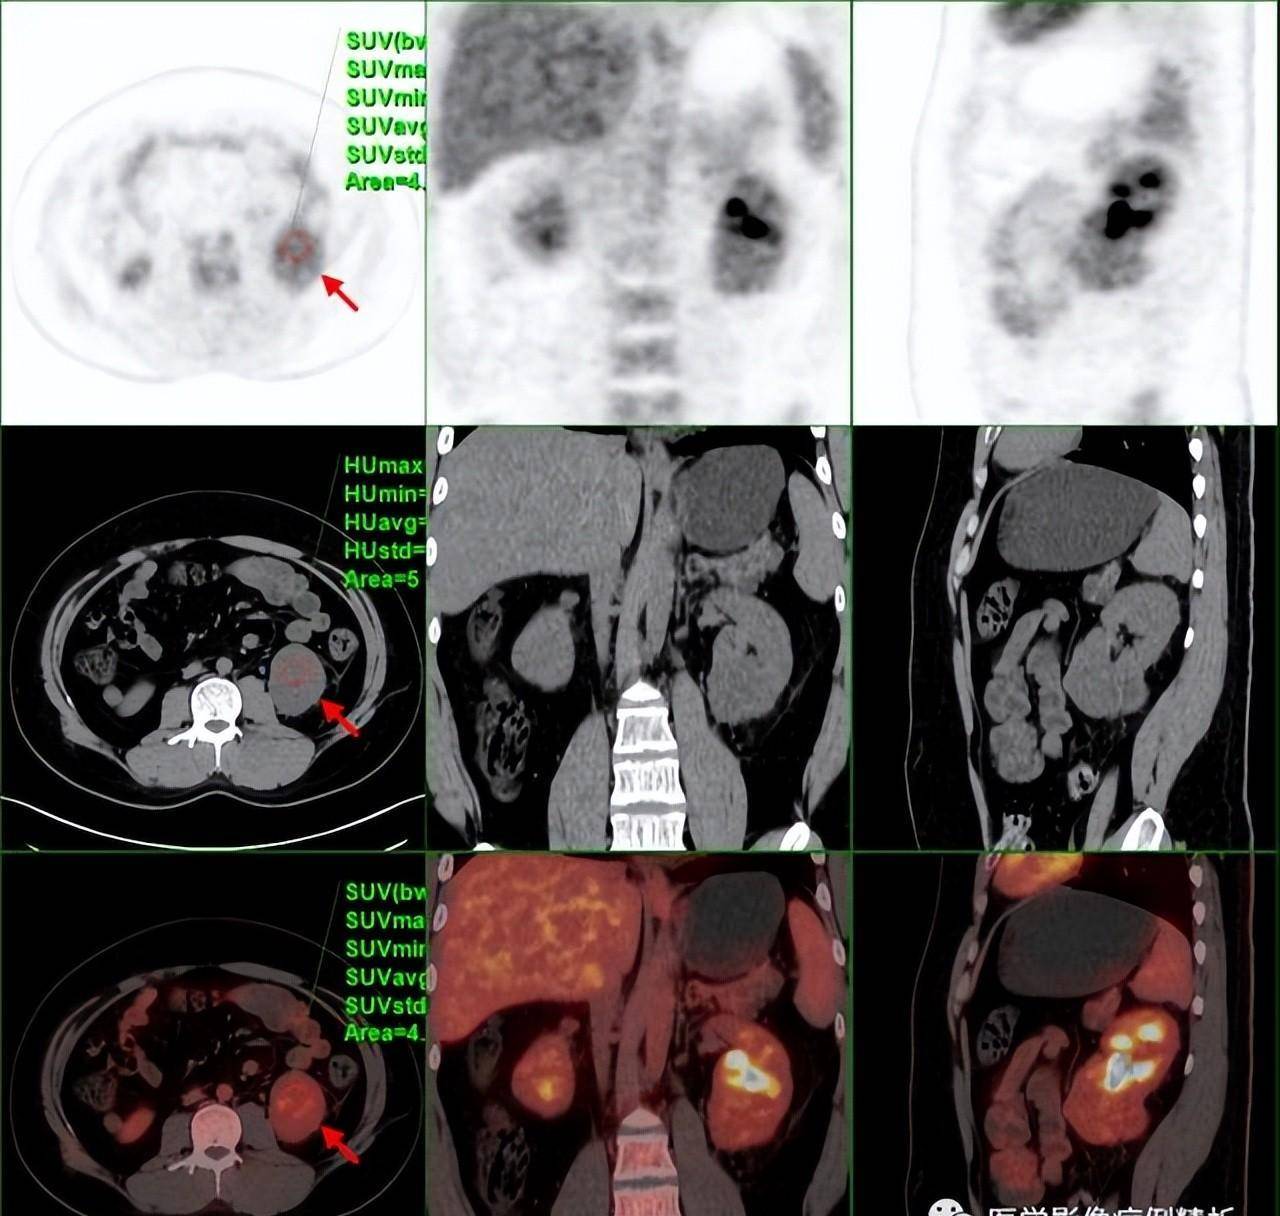

vhl综合征(林岛综合征)pet-ct影像诊断及鉴别诊断_病变_代谢_分析